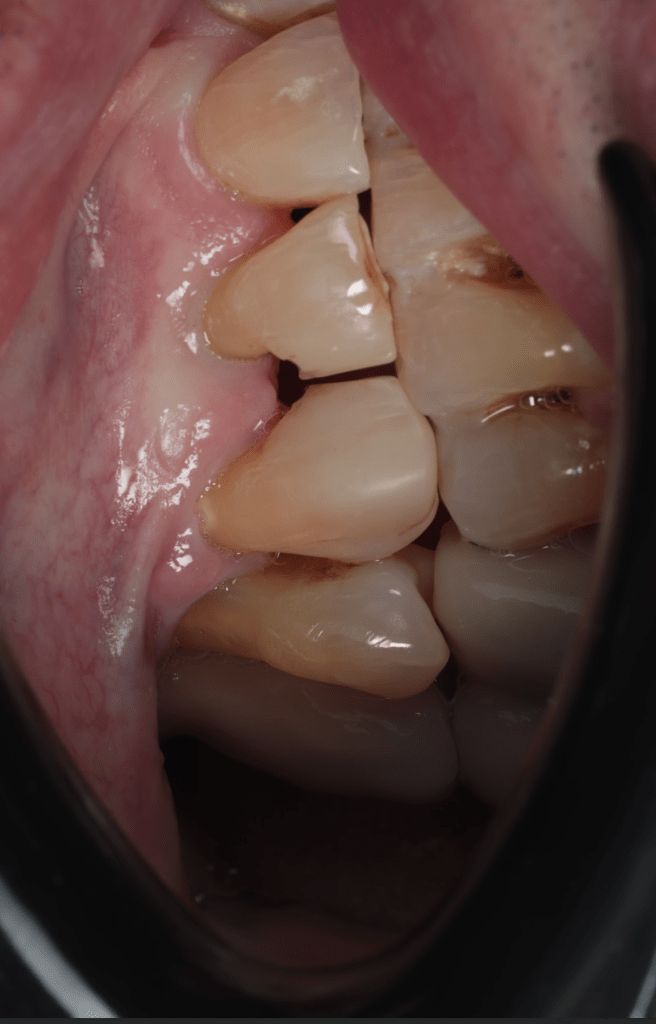

Diagnóstico de fisuras y fracturas

Diente fisurado tratable

Diente fisurado tratable con endodoncia

Diente fisurado tratable endodoncia 2

Fractura cuspídea tratable